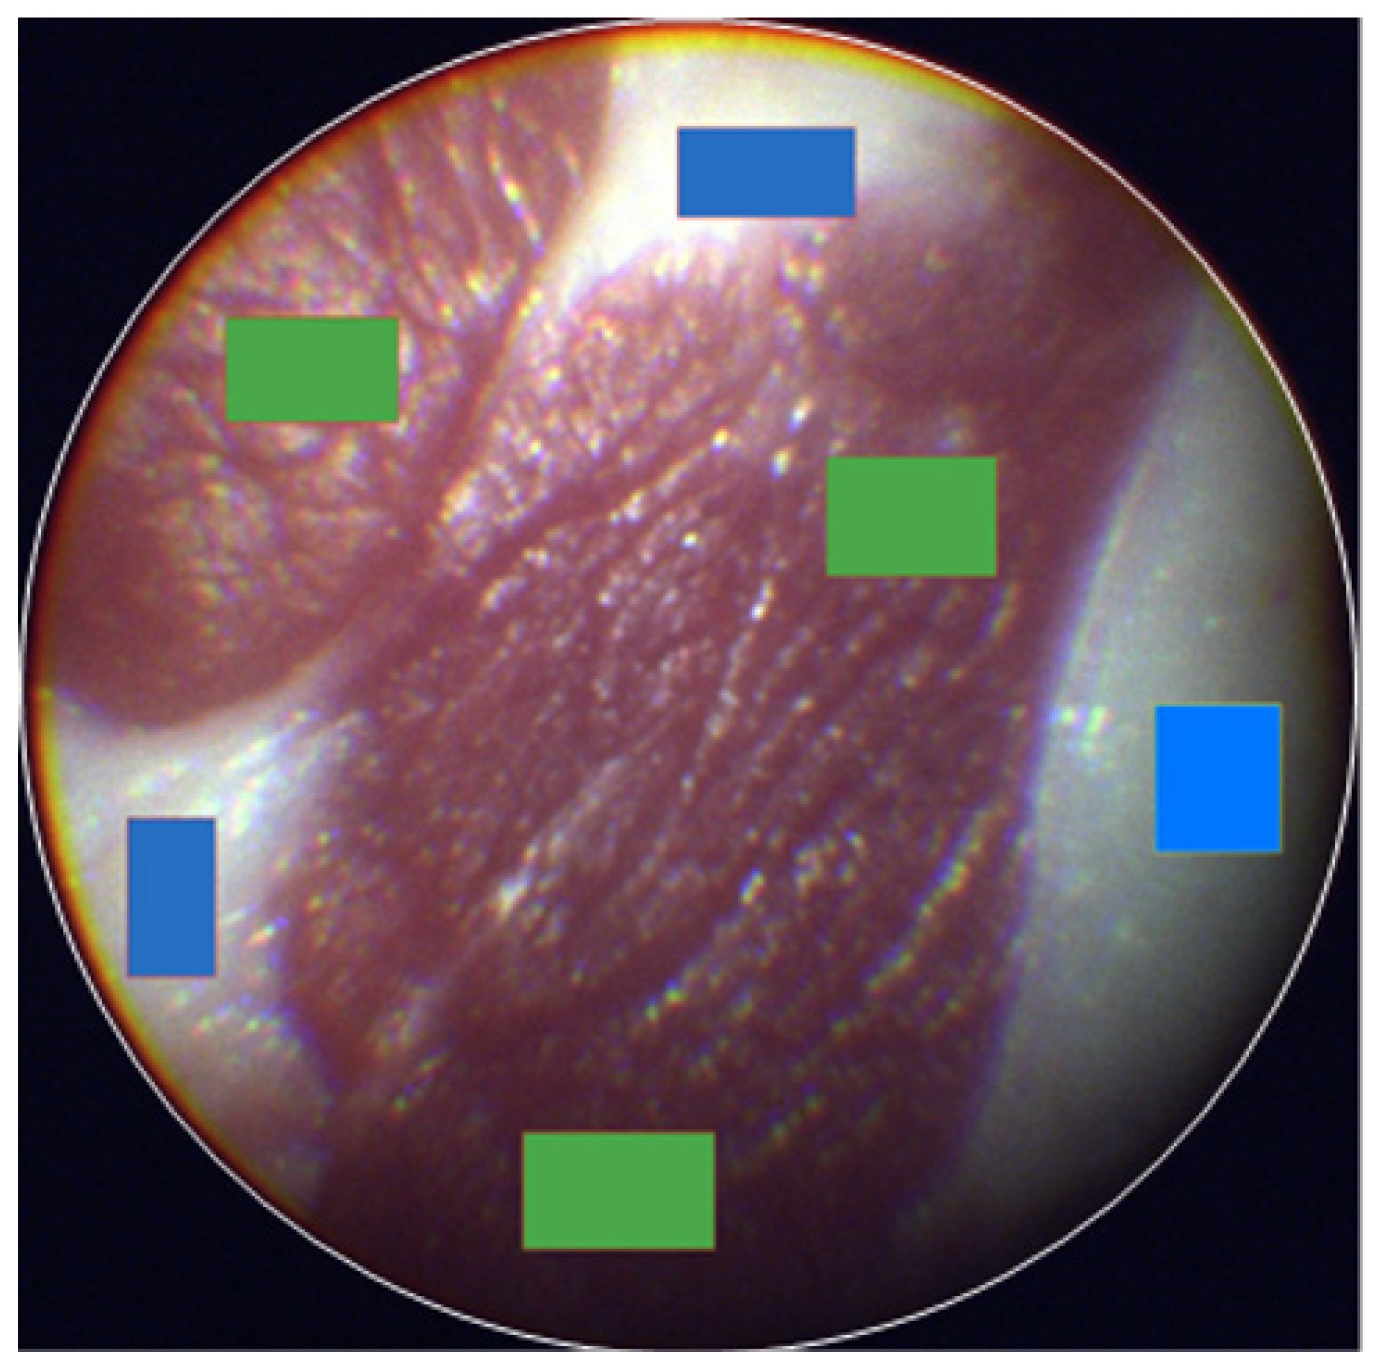

Figure 2.

Image classification of eHSI in a tissue phantom. The muscle (green rectangle) and fat (blue rectangle) of tissue phantoms were labeled with multiple rectangular regions of interest (ROIs).